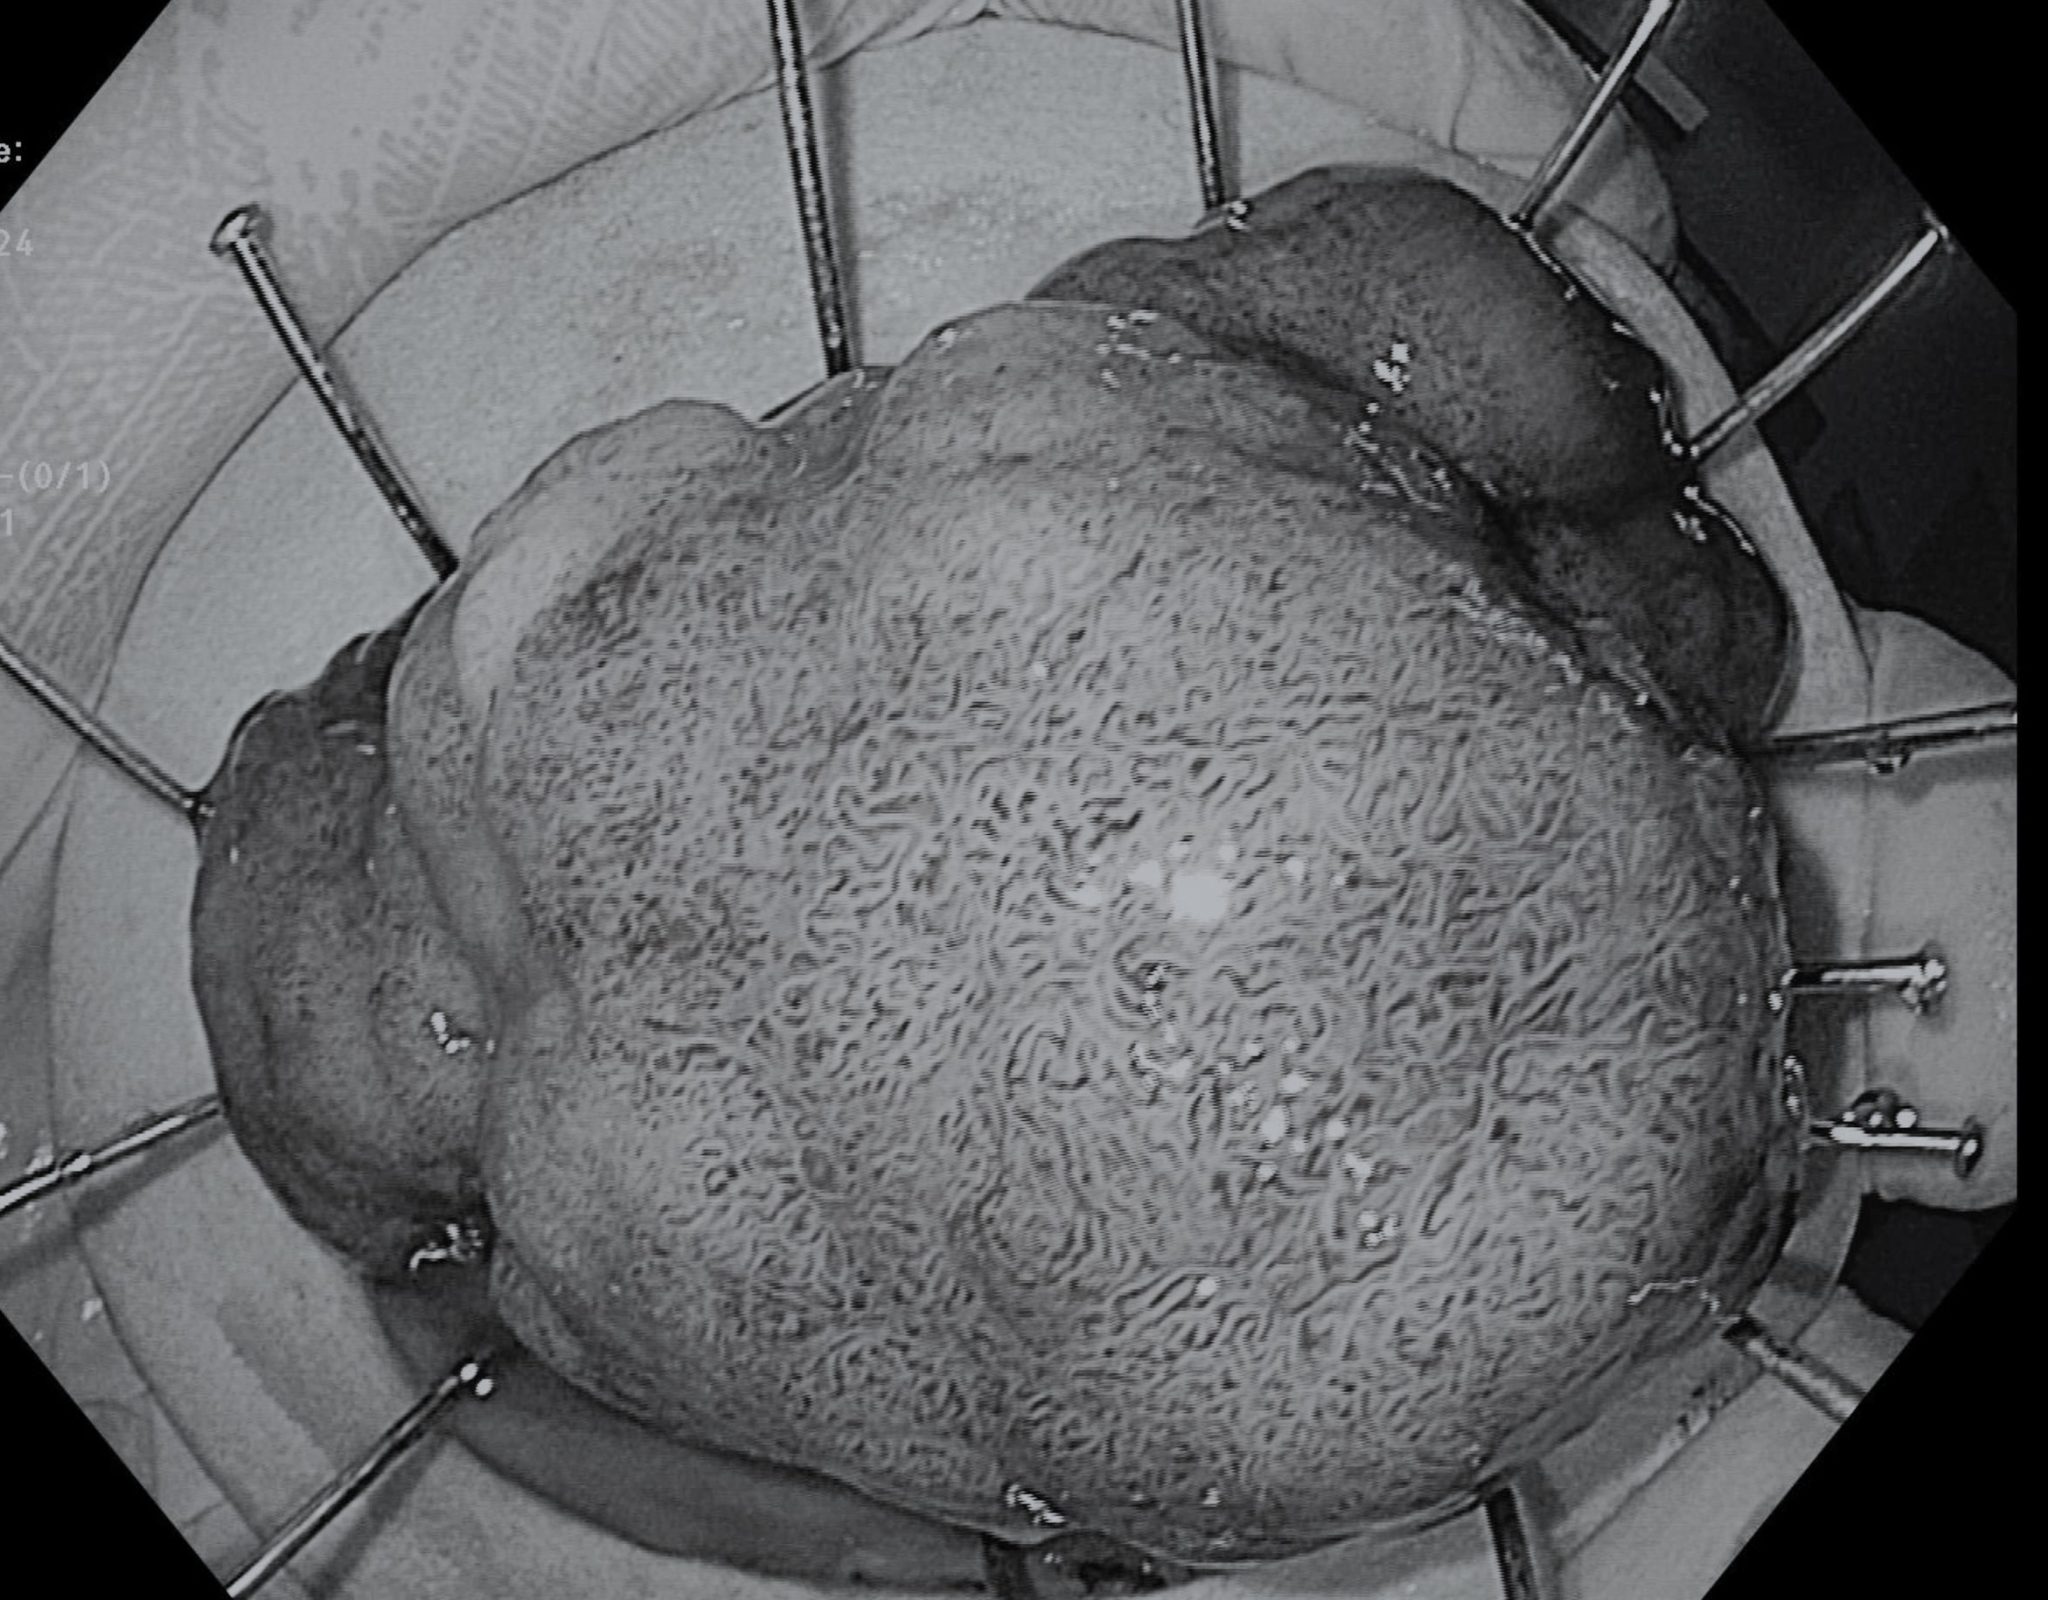

Bệnh nhân nam đi khám với tình trạng đại tiện phân lỏng nhày ngày càng tăng. Sau khi thực hiện nội soi tiêu hóa, bác sĩ phát hiện người bệnh có khối Polyp lấp lòng đại tràng Sigma đoạn nối với trực tràng, kích thước 5cm; bề mặt Polyp chưa nghĩ tới ung thư xâm lấn.

Chưa tới 90 phút gây mê, bệnh nhân đã được can thiệp qua nội soi lấy thành công khối u kích thước 5cm. Theo dõi sau can thiệp, người bệnh không đau, không chảy máu, hoàn toàn ổn định. Kết quả giải phẫu bệnh xác định ung thư sớm xâm nhập mô đệm PT1a, diện cắt âm tính, không xâm lấn mạch và bạch huyết.